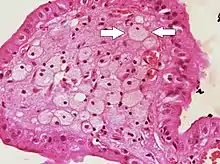

![]() | Foam cells | Histopathology of cholesterolosis of the gallbladder, with annotated foam cell | Category: Foam cell | Foam cell |